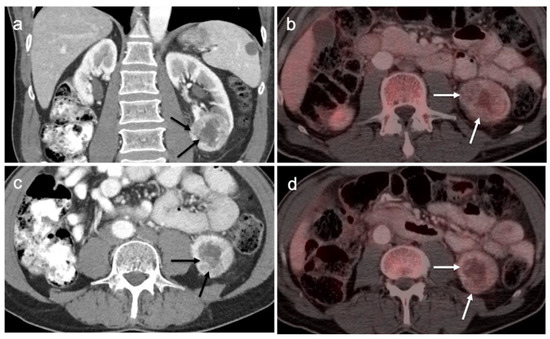

3.5. Penile Cancer